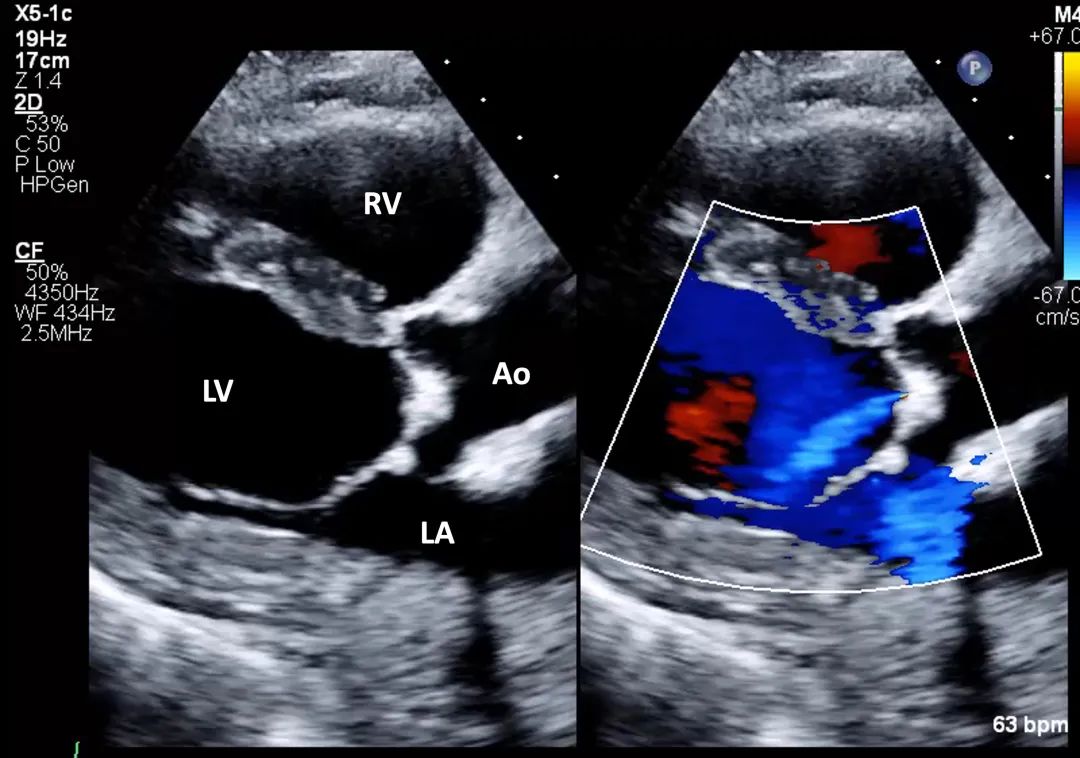

2、 在胸骨旁长轴切面放大(zoom)主动脉瓣(AV)和二尖瓣结构,分别采用普通二维和彩色多普勒模式进行评估(图3,视频2)。

图3. 胸骨旁长轴切面放大图像(普通二维和彩色多普勒对比)

胸骨旁长轴切面下主动脉瓣的放大图像,分别展示使用普通二维和彩色多普勒的情况。缩写同图2。

视频2. 胸骨旁长轴切面应用彩色多普勒(彩色与二维灰阶对比模式),评估主动脉瓣是否存在反流及主动脉瓣狭窄时典型的彩色镶嵌血流模式。